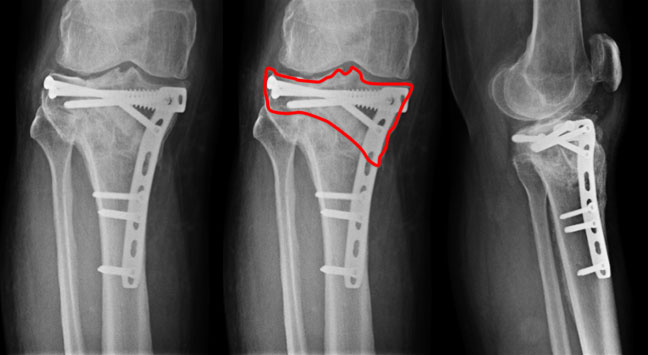

| The x-ray picture at 1 year after reconstruction. The fracture is healed well. There is no articular step now. The osteoporosis of the bones has reduced markedly. |